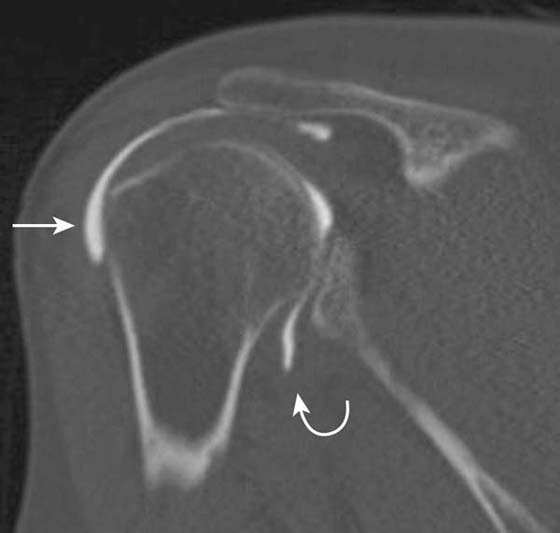

Although shoulder impingement is a clinical diagnosis, it has imaging manifestations that are helpful in guiding treatment. Radiography plays a role in the initial examination of impingement. Subacromial spurs, glenohumeral joint osteoarthritis, and evidence of chronic rotator cuff tear with a high riding humeral head may be identified with radiographs,5 which may further influence management decisions (Fig. 14-6). Noncontrast shoulder MRI is frequently employed in the assessment of impingement. Manifestations of impingement, such as subacromial spur, subacromial/subdeltoid (SASD) bursitis, and rotator cuff tears, are all easily demonstrated on MRI.15-17 Features of a rotator cuff tear that can be assessed on MRI include tear type (full vs. partial thickness), tear location, tear dimensions, tear morphology, tear gap/degree of tendon retraction, and the presence of rotator muscle atrophy (Fig. 14-7).

images

Figure 14-6 Chronic rotator cuff tear. Anteroposterior radiograph of the shoulder demonstrates severe narrowing of the acromiohumeral distance (arrow), indicating chronic rotator cuff tear. Marked subacromial spur formation is also seen. An MRI was contraindicated in this patient due to the presence of a cardiac pacemaker.

Figure 14-7 Full-thickness rotator cuff tear. Coronal fat-suppressed T2-weighted MRI of the shoulder demonstrates a large tear of the supraspinatus tendon. The tendon is torn, frayed, and retracted back, almost to glenohumeral joint level (arrow).

US is also a valuable tool in the assessment of impingement18 and is useful for the evaluation of rotator cuff pathology (Fig. 14-8) although it cannot give a global assessment including labral, capsular, cartilage, and marrow pathology. US is useful in the setting of rotator cuff repair and is particularly useful in shoulder arthroplasty where susceptibility artifact from the metallic prosthesis on MRI would limit interpretation of the adjacent cuff.19 In addition, calcific tendinosis of the rotator cuff is well demonstrated on US20 and is often amenable to SASD bursal injection of steroid and anesthetic or needling in refractory cases.

Figure 14-8 Partial-thickness rotator cuff tear. Ultrasound along the long axis of the distal supraspinatus tendon adjacent to its insertion on the greater tuberosity demonstrates a focal partial undersurface tear (arrow) as indicated by a hypoechoic (dark) defect.